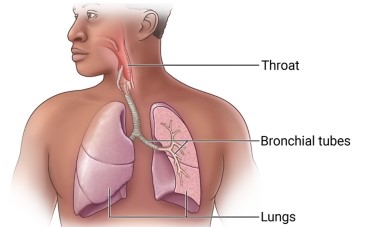

What Is Aspiration Pneumonia?

Aspiration Pneumonia is a type of pneumonia that results from inhaling foreign substances into the lungs, which can lead to bacterial infection. The condition is often linked to conditions that impair swallowing or the protective reflexes of the airway. Aspiration can occur during eating, drinking, vomiting, or even while lying down, particularly in those with certain medical conditions.